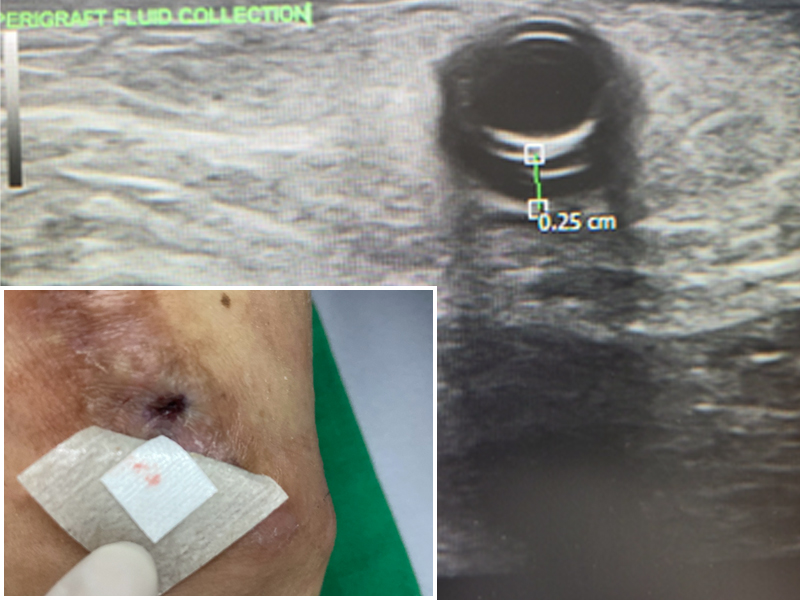

인공신장실 30년 경력의 수간호사 선생님과 18명의 투석실 간호사님이 세심한 혈관관리를 하고 문제시 초음파를 통한 조기 진단과 치료를 하고 있습니다.